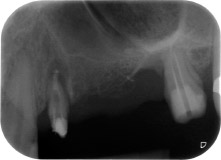

apical periodontal lesion at tooth 24

Fig. 1: 58-year-old patient. Preoperative radiograph showing an apical periodontal lesion at tooth 24 and horizontal loss of alveolar bone in the second quadrant.

A 58-year-old female patient complained of pain and increased mobility of her bridge abutment tooth 24. Periodontal inflammation was present with pocket depths of 7 mm mesiobuccally and more than 12 mm distally, as well as third-degree furcation involvement. Moreover, the radiograph revealed an extensive periodontal lesion around the apical region of the (alio loco) endodontically pretreated tooth 24 (Fig. 1).

Postoperative radiograph

Fig. 16: Postoperative radiograph showing the implants in place, with bone substitute material from the internal sinus lift around the apices. There is some material from the GTR procedure visible around the roots of tooth 24.